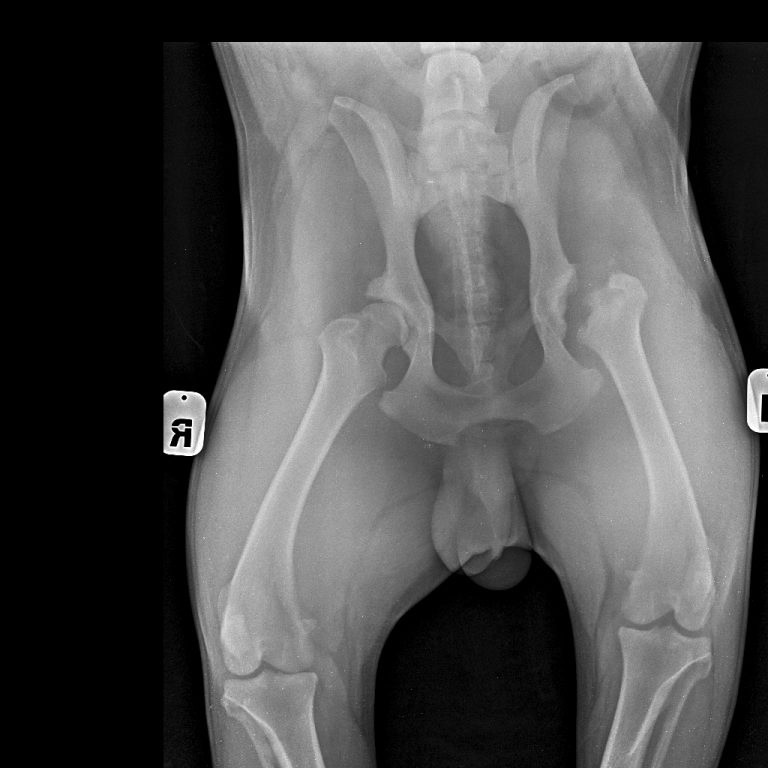

Хирургическое вмешательство, которое помогает сохранить сустав относительно здоровым, называется Ювенильный симфизиодез: производится разрез в районе лонных костей и область лонного симфиза прижигается определенным образом специальным прибором — эта манипуляция не дает костям таза разворачиваться в «неправильном» направлении. Рентгеновский снимок лабрадора через 7 месяцев после такой операции. Как видим, тазобедренные суставы сформировались без явных отклонений, несмотря на явный положительный тест Ортолани в 13 недельном возрасте.

Рентгенография является основным методом диагностики дисплазии тазобедренных суставов. При проведении рентгенологического исследования животное располагается на спине с вытянутыми тазовыми конечностями.

На рентгенограмме в зависимости от степени дисплазии (А, B, C, D, E) определяются различные рентгенологические признаки. Впервые рентгенологическая оценка ДТБС была дана в 1966 году Ортопедическим фондом животных образованным John Olin.